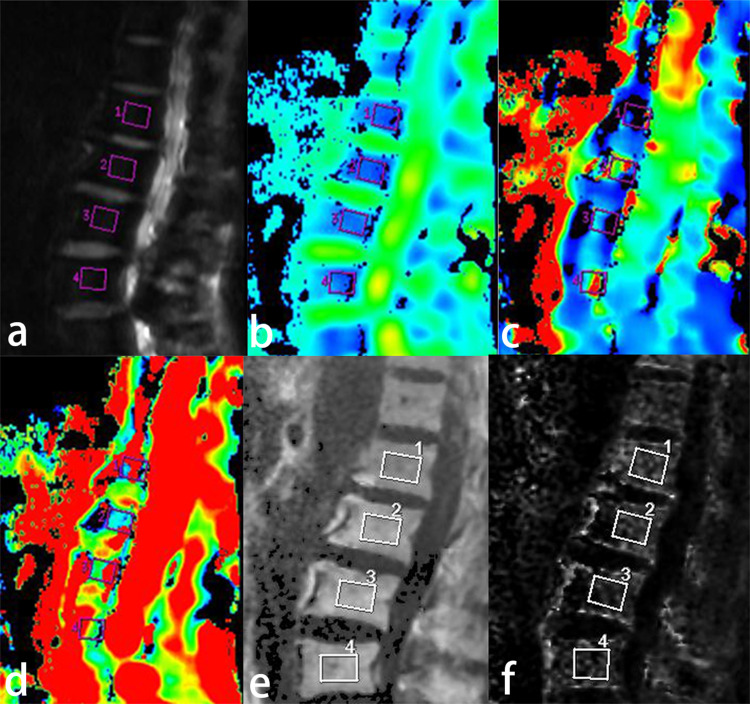

Methods: A total of 346 patients (50-87 years, 232 females, 114 males) underwent spinal DEXA and MRI. Based on the BMD obtained from DEXA, the patients were stratified into: normal (n=79), osteopenia (n=92), and OP (n=175) groups. Then to evaluated the results of IVIM-DWI and IDEAL-IQ and extracted quantitative parameters from regions of interest covering the L1 to L4 vertebrae. Group comparisons used One-way analysis of variance and the Kruskal‒Wallis H-test. Receiver operating characteristic (ROC) and Spearman's analyses evaluated diagnostic performance and correlations.

Results: Significant differences existed in the ADCslow, f, FF and R2* between groups (P<0.05). BMD was weakly positively correlated with ADCslow, f, and R2* (r=0.494, 0.153, 0.182, 0.029, P<0.001) but a negative correlation with FF (r=-0.402, P<0.001). BMD and the ADCslow and R2* decreased but FF increased with age (P<0.05 for all), whereas no significant association existed between age and ADCfast or f value (P>0.05). FF had the highest areas under the curve (AUCs) (0.624, 0.831 and 0.747) and sensitivity (72.2%, 70.9% and 81.5%) in differentiating normal from osteopenia patients, normal from osteoporosis patients, and osteopenia from osteoporosis patients, respectively. ADCslow and f had the highest specificity (88%) in differentiating between normal and osteopenia patients, while ADCslow had the highest specificity (91.4%) in differentiating between normal and osteoporosis patients.